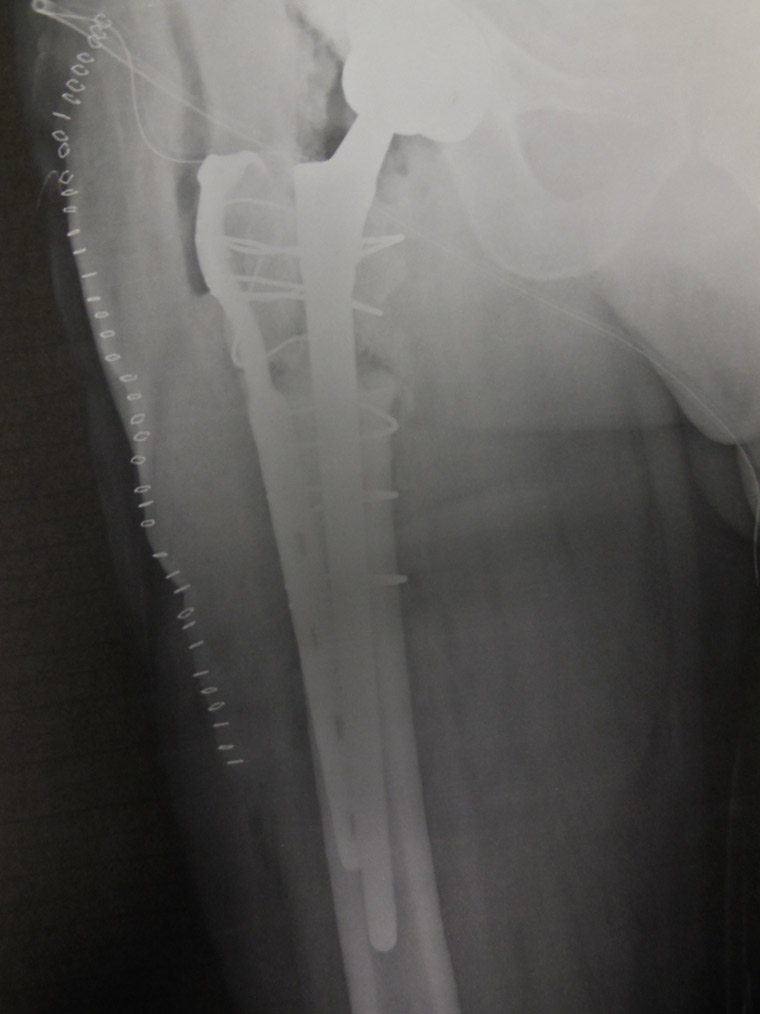

Fig.2 Radiografia postoperatoria. I cerchiaggi e la placca sono stati utilizzati per richiudere il femore dopo che esso è stato “aperto” per rimuovere la protesi. Una volta chiuso il femore, si procede al posizionamento dello stelo protesico lungo che deve far presa sulla porzione di femore sano. E’ stato ovviamente cambiato anche il cotile. Trattasi di intervento assai impegnativo.